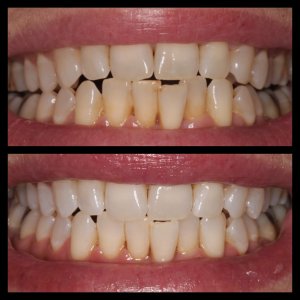

ΛΕΥΚΑΝΣΗ ΔΟΝΤΙΩΝ